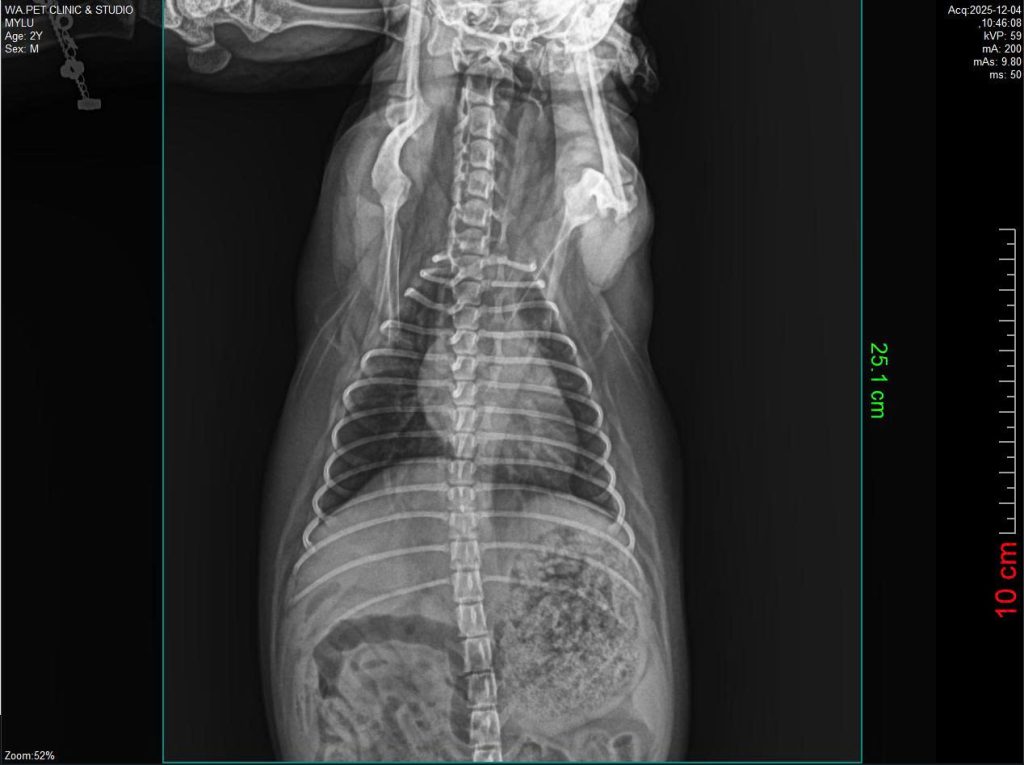

Phòng khám thú y Wa cung cấp dịch vụ siêu âm và X-quang với đầy đủ trang thiết bị hiện đại, hỗ trợ chẩn đoán hình ảnh chính xác, phát hiện sớm các vấn đề sức khỏe nội khoa và ngoại khoa.